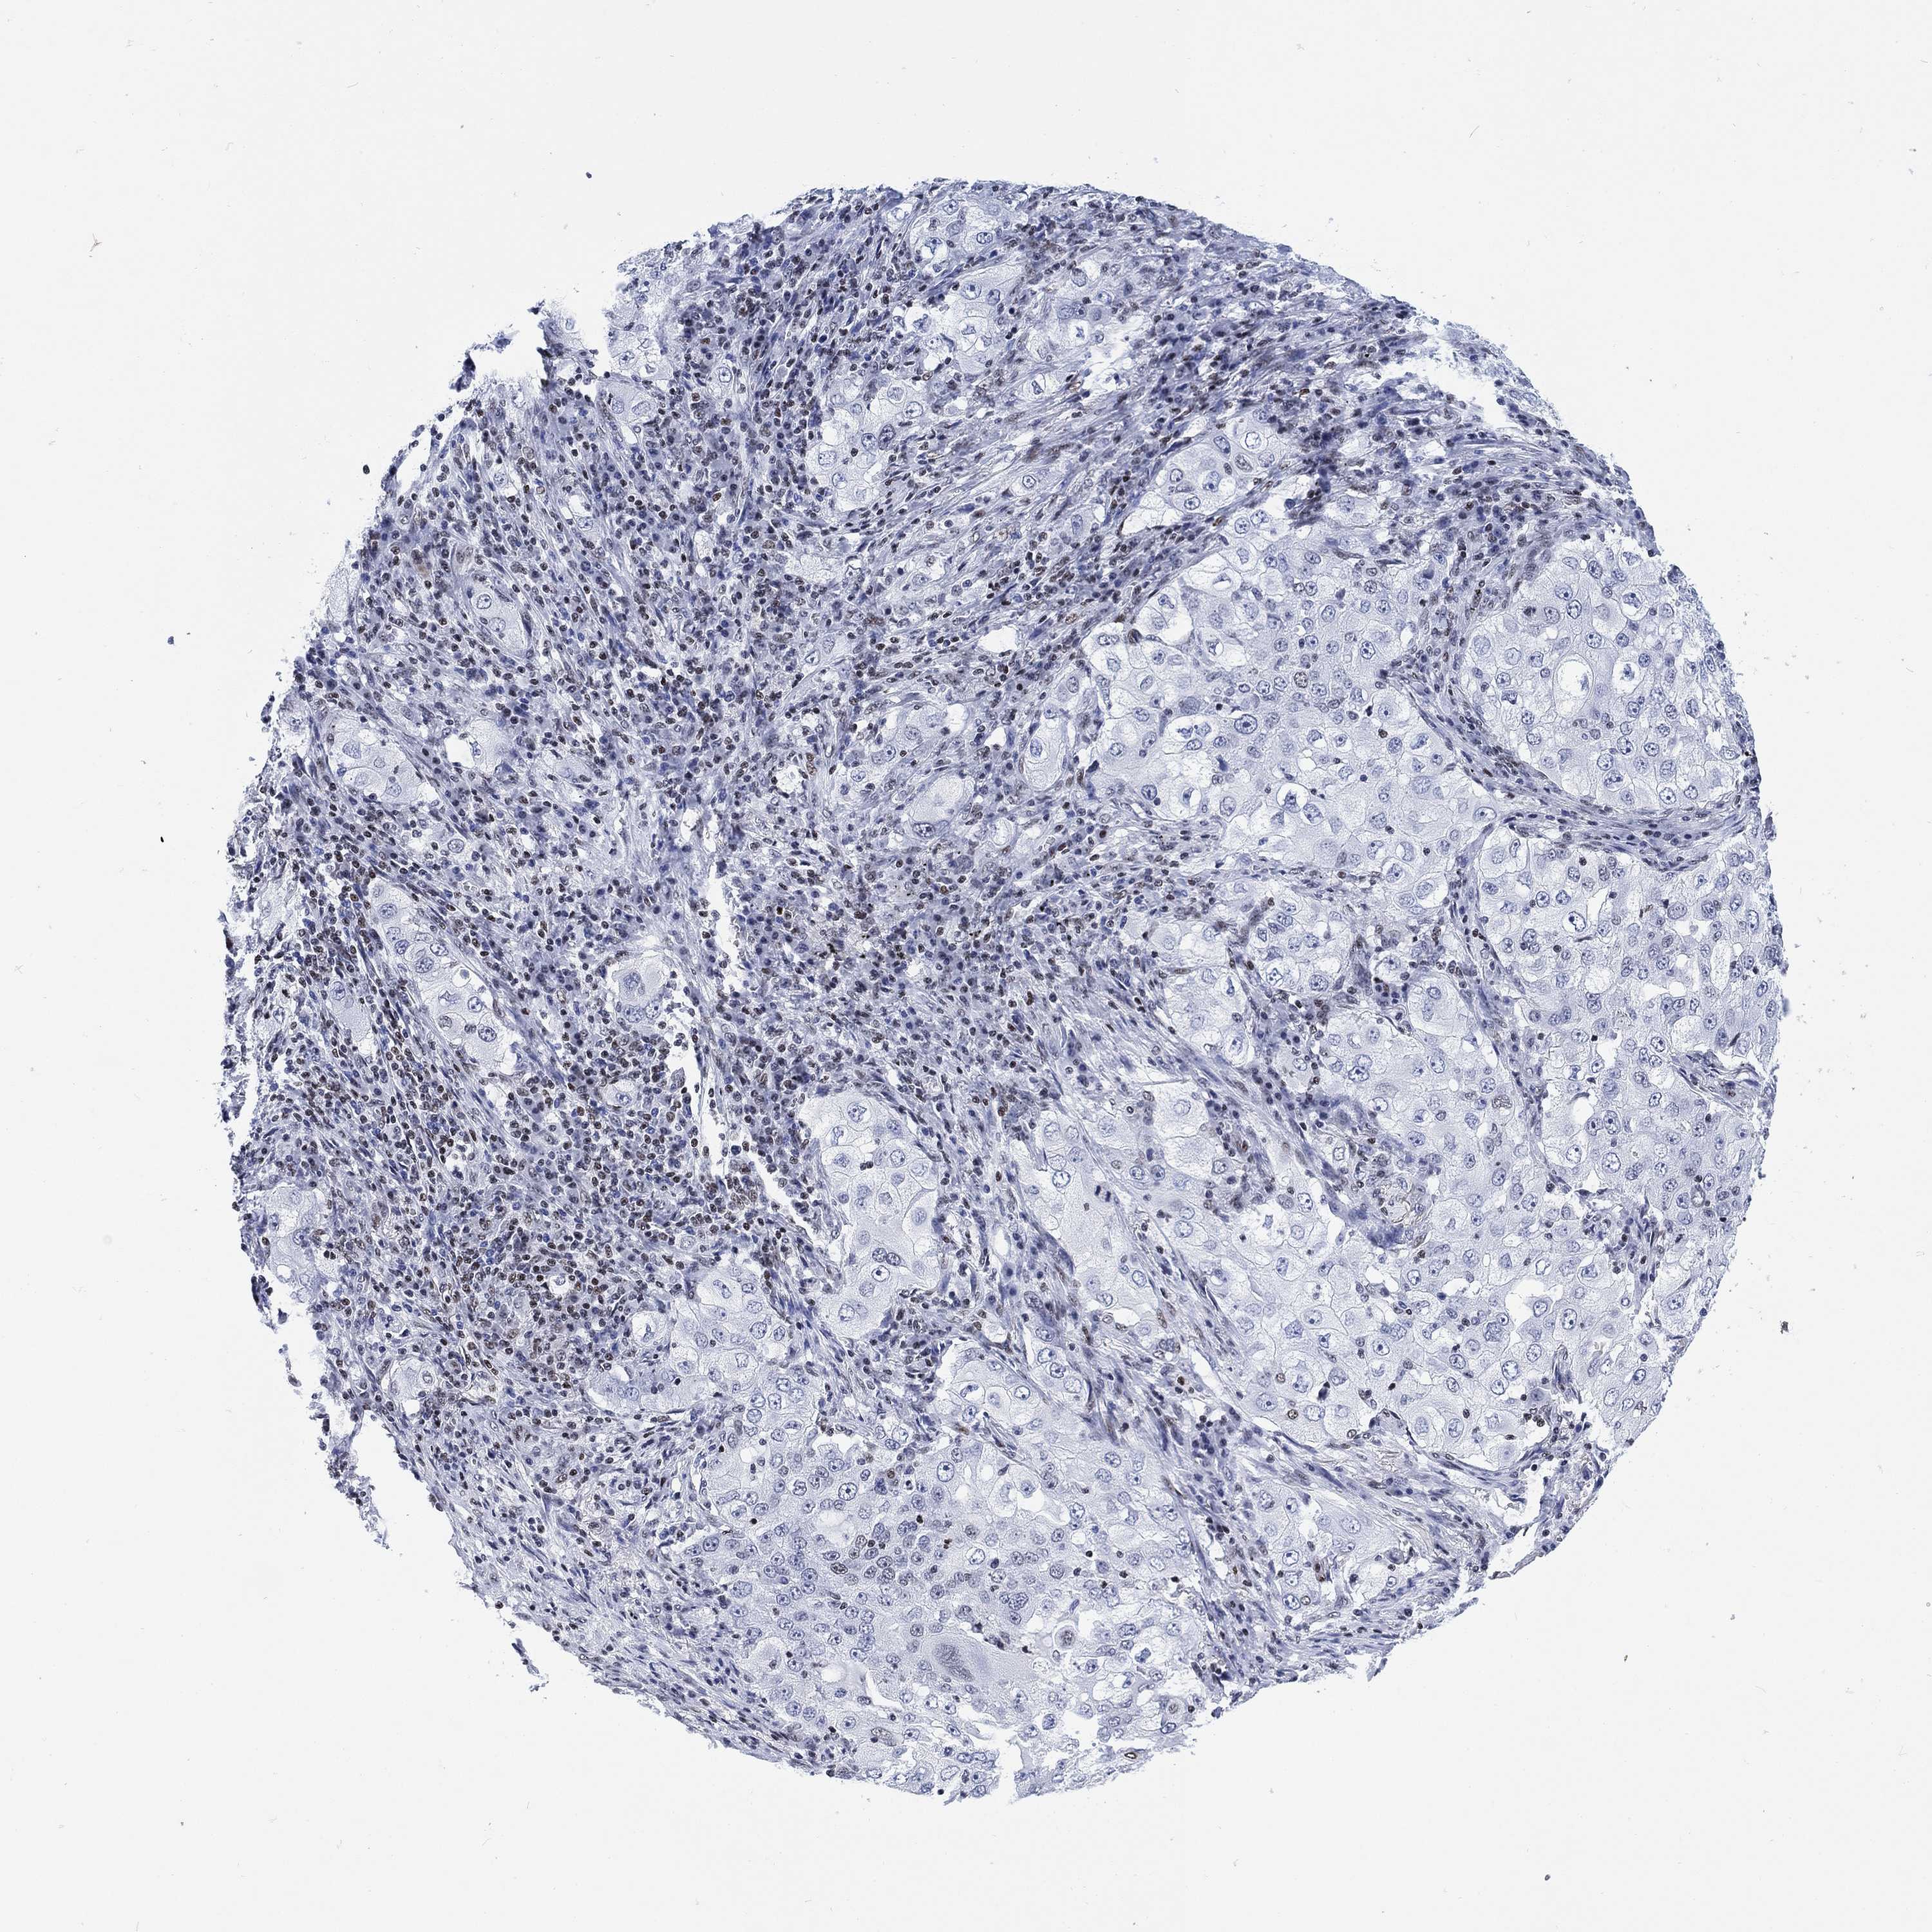

CANCER LUNG CANCER Show tissue menu

H1-10 is not prognostic in Lung Squamous Cell Carcinoma (TCGA)

Stage: